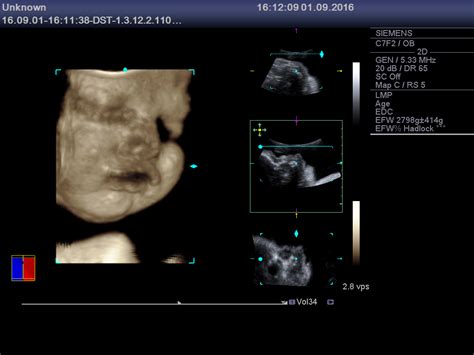

1. Ecografia

Este o metodă non-invazivă de a determina sexul copilului și se face de obicei între săptămânile 18 și 22 de sarcină. Ecografia poate să nu detecteze întotdeauna sexul dacă poziția copilului nu este ideală sau dacă sarcina nu a progresat. În aceste cazuri, este posibil să fie necesară repetarea ecografiei.